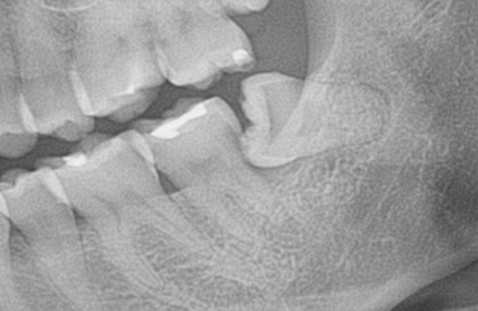

1.上も下も親知らずが半分しか頭を出さず、その周りに磨き残しが出来てしまいます

親知らずに歯肉がかぶさり、ブラッシングが思うように出来ません。虫歯と歯槽膿漏になる可能性が高くなります。

前の歯の陰に隠れて親知らずまで歯ブラシが届かず、汚れがいっぱい残っています。